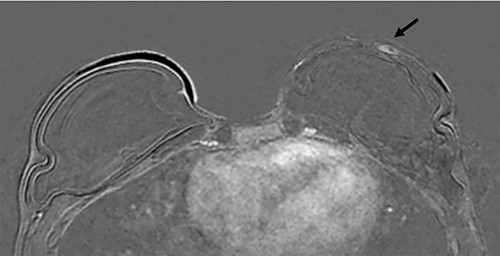

Clinical findings during follow-up were unremarkable until 2020, when she represented with a new lump in the reconstructed left breast neighbouring the mastectomy scar inferiorly. A 1 cm subcutaneous lump with no skin tethering, was palpable along the uniting suture line of the ADM-pectoral muscle. Imaging with ultrasound was indeterminate. This implant proximity rendered it unsuitable for core biopsy due to the high risk of iatrogenic implant perforation (Fig. 2). Subsequent MRI (Fig. 3) illustrated an 11 mm low signal lesion correlating clinically to the palpable lump with mild enhancement but indeterminate appearance.

Axial post contrast fat-saturated sequence identified bilateral implants and an 11 mm oval foci of type 1 enhancement in the site of clinical concern on the capsule (black arrow).